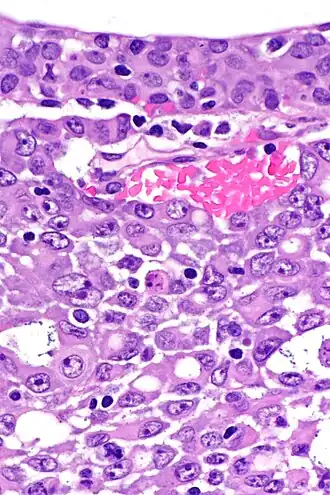

![]() Типичная гистологическая картина медуллярного рака почки в высоком разрешении. Окраска гематоксилином и эозином. | |

Гистологически эти опухолевые поражения имели либо вид ретикулярных опухолей, напоминающих злокачественные опухоли, происходящие из желточного мешка, либо вид аденоидно-кистозных опухолей. Часто отмечались островки низкодифференцированной опухолевой ткани, с сильно десмопластической стромой. Отмечались выраженная воспалительная реакция как в самой ткани опухоли, так и в окружающих её тканях, внутриопухолевый и перифокальный отёк, инфильтрация ткани опухоли нейтрофильными гранулоцитами, а также окаймление её воспалительным «валиком» из лимфоцитов[8].